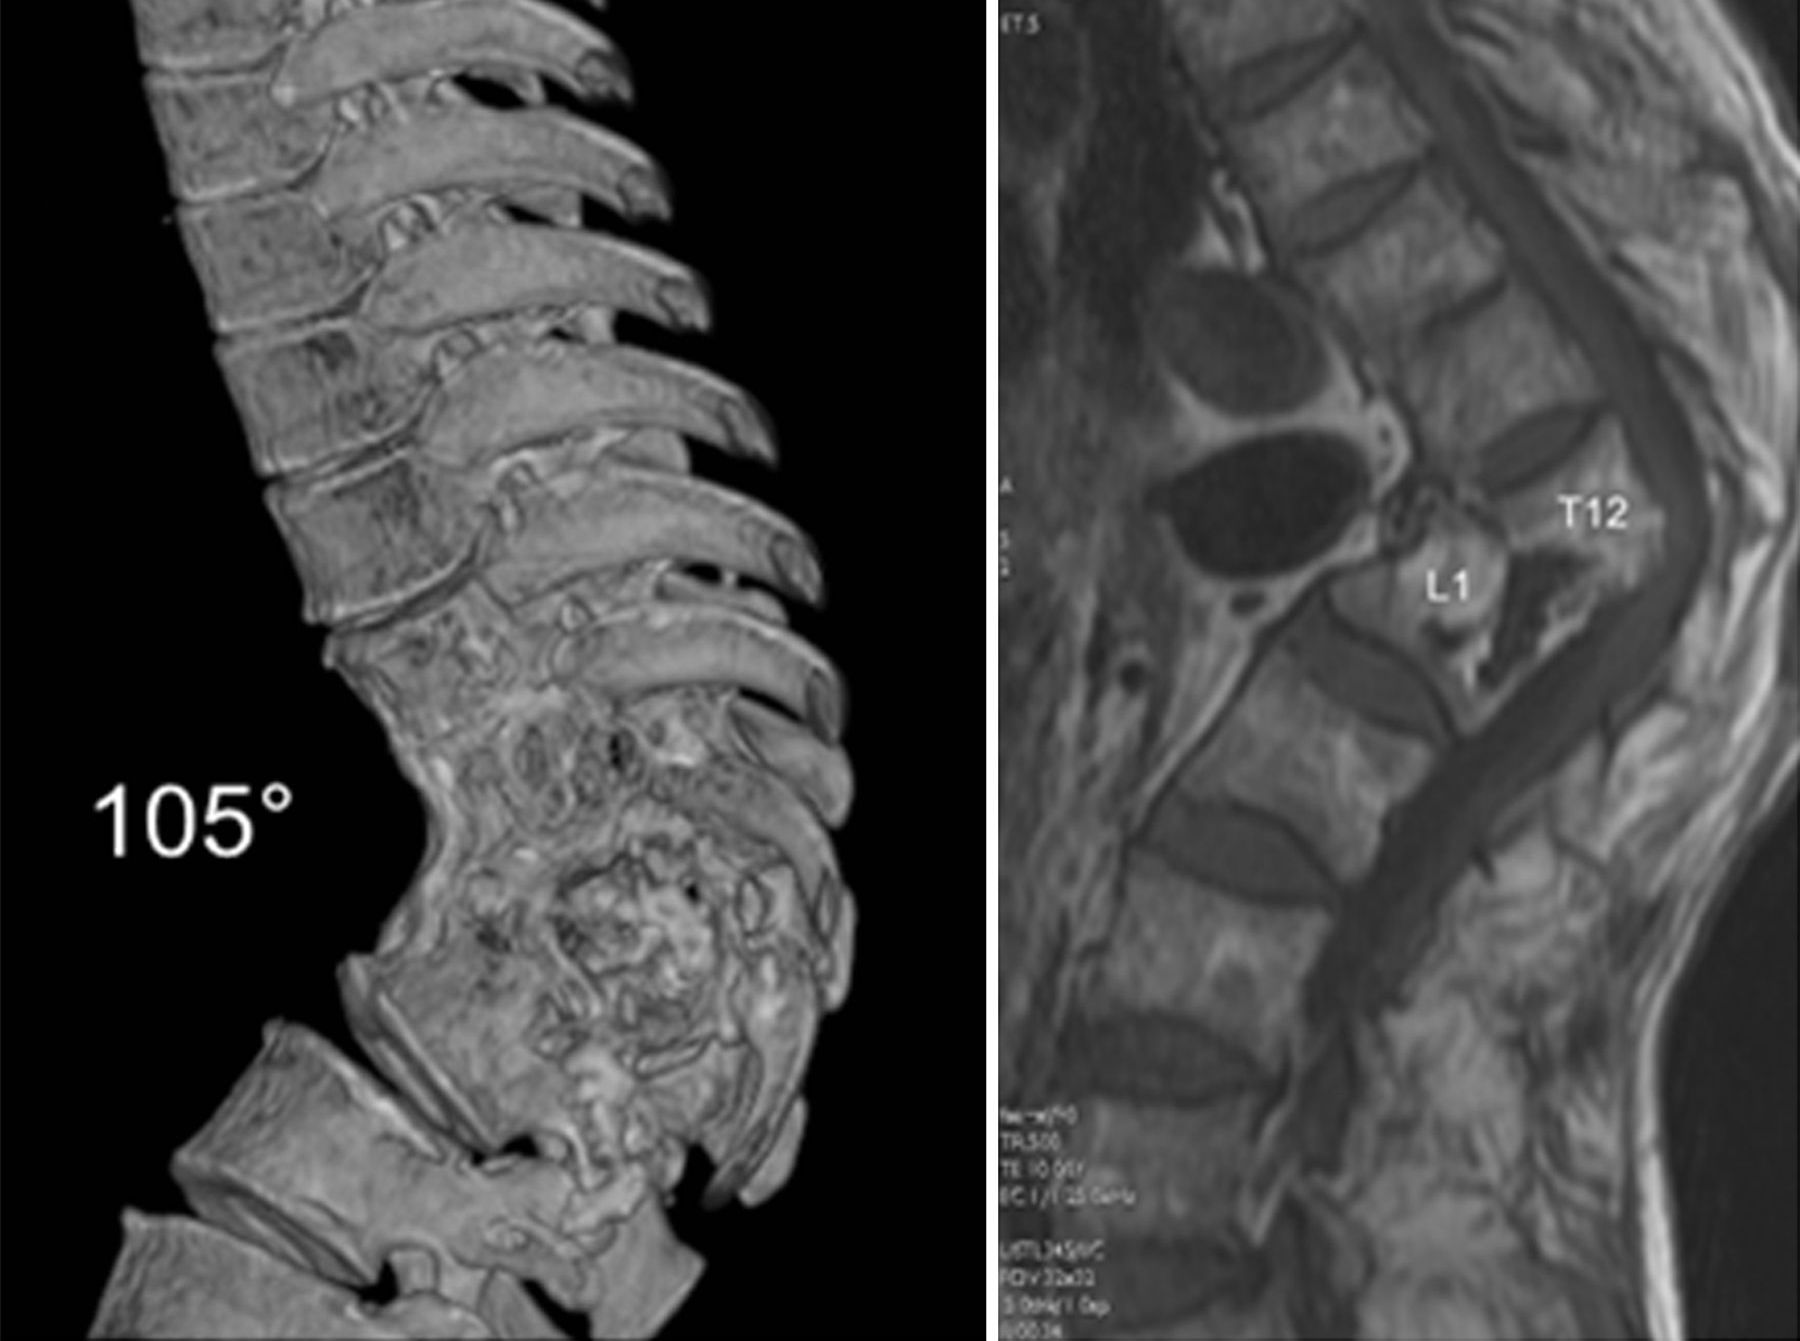

Η φυματίωση της σπονδυλικής στήλης παρουσιάζεται με «κατάγματα συμπίεσης».

Ο πόνος στην πλάτη είναι ένα σημαντικό σύμπτωμα. Η απεικόνιση με μαγνητικό συντονισμό (MRI) είναι μια πολύ καλή εξέταση για τη διάγνωση της φυματίωσης της σπονδυλικής στήλης. Ωστόσο, η μικροβιολογική διάγνωση είναι απαραίτητη (PCR). Το Mycobacterium tuberculosis μπορεί να καλλιεργηθεί από άλλους τόπους λήψης. Σε αντίθετη περίπτωση, βιοψία της βλάβης στη σπονδυλική στήλη θα πρέπει να γίνει για την παθολογική διάγνωση. Οι κλινικοί γιατροί θα πρέπει να εξετάσουν τη νόσο Pott στην διαφορική διάγνωση των ασθενών με οσφυαλγία και βλάβες των σπονδύλων.

- Η φυματιώδης σπονδυλίτιδα οδηγεί σε κύφωση

- Προκαλεί συμπίεση του νωτιαίου μυελού